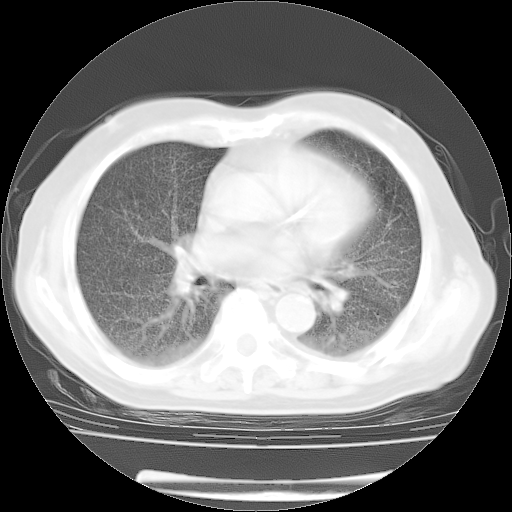

4月14日肺部CT

23.JPG

24.JPG

25.JPG

26.JPG

肺部CT平扫未见异常。